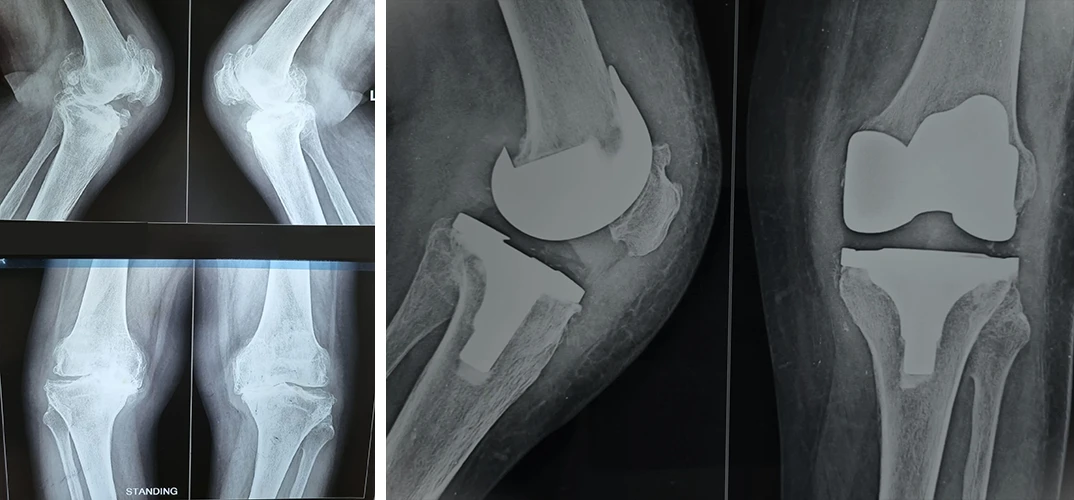

Total Hip & Knee Arthroplasty

Total Knee Replacement

Are you having pain in your knees? Look no further, because Dr. Sanyal is the best choice for you. He specialises in total knee replacement surgery, offering you a solution to regain your mobility and live pain-free.